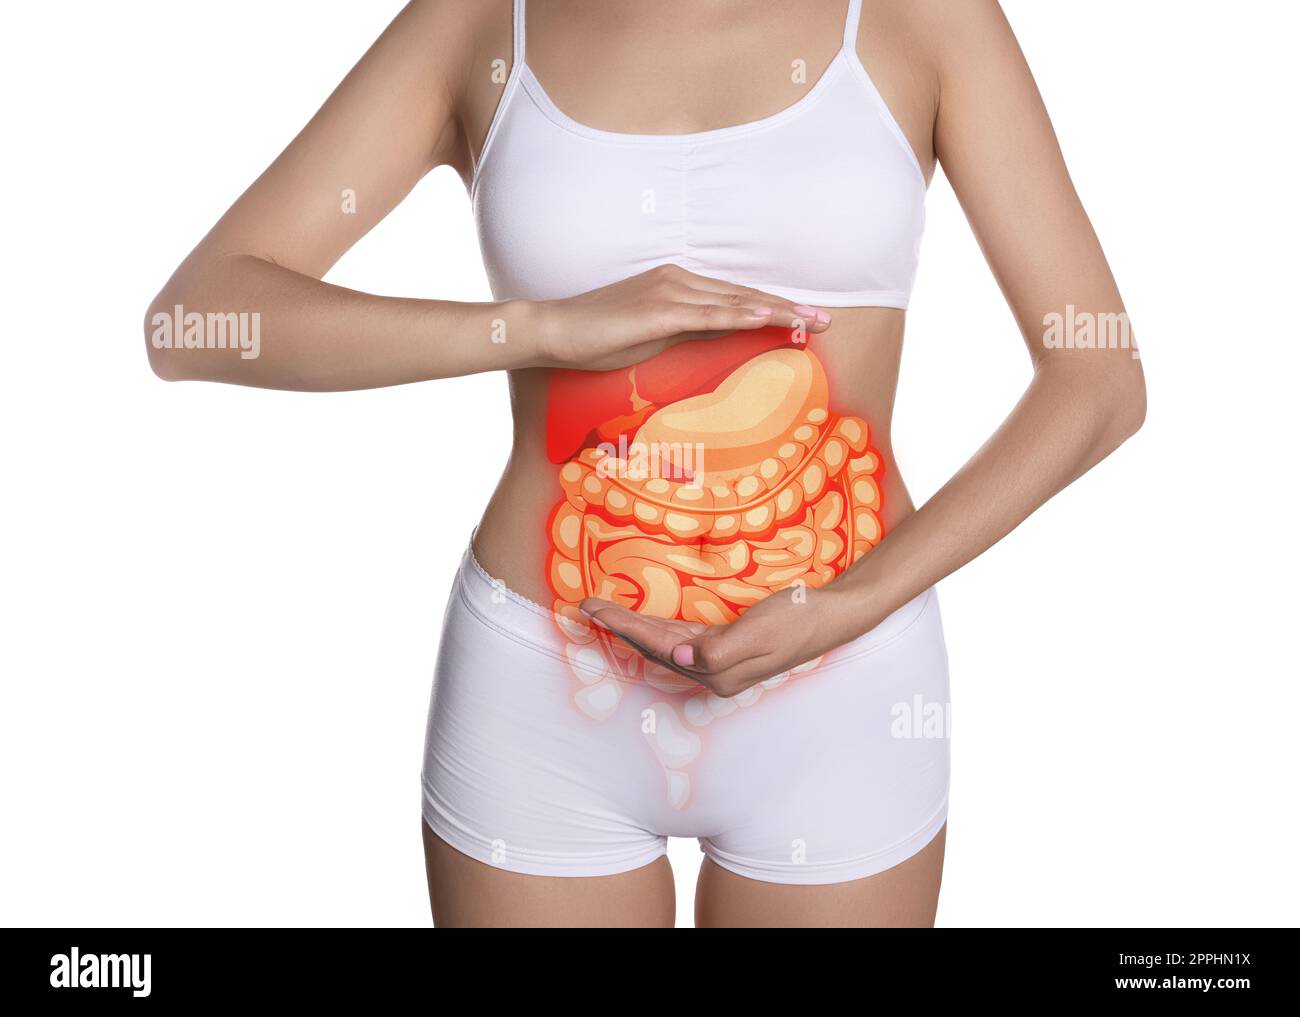

Vue rapprochée de la femme avec illustration des organes abdominaux sur son ventre sur fond blanc Banque D'Imageshttps://www.alamyimages.fr/image-license-details/?v=1https://www.alamyimages.fr/vue-rapprochee-de-la-femme-avec-illustration-des-organes-abdominaux-sur-son-ventre-sur-fond-blanc-image547433542.html

Vue rapprochée de la femme avec illustration des organes abdominaux sur son ventre sur fond blanc Banque D'Imageshttps://www.alamyimages.fr/image-license-details/?v=1https://www.alamyimages.fr/vue-rapprochee-de-la-femme-avec-illustration-des-organes-abdominaux-sur-son-ventre-sur-fond-blanc-image547433542.htmlRF2PPHN1X–Vue rapprochée de la femme avec illustration des organes abdominaux sur son ventre sur fond blanc